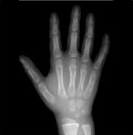

4) 같은 또래 아이들의 키보다 2표준편차 이상 작은 경우에는 성장클리닉 전문의의 진료가 필요합니다. 키가 정확히 또래 아이들보다 작은편인지 큰 편인지 진료를 통해 알아볼 수 있으며 성장판 촬영으로 골연령을 정확히 측정하는 것이 중요합니다.

| 열린경우 | 닫혀가는 경우 | 닫힌 경우 | |

| 경골 Tibia |

| 지골 Phalange |